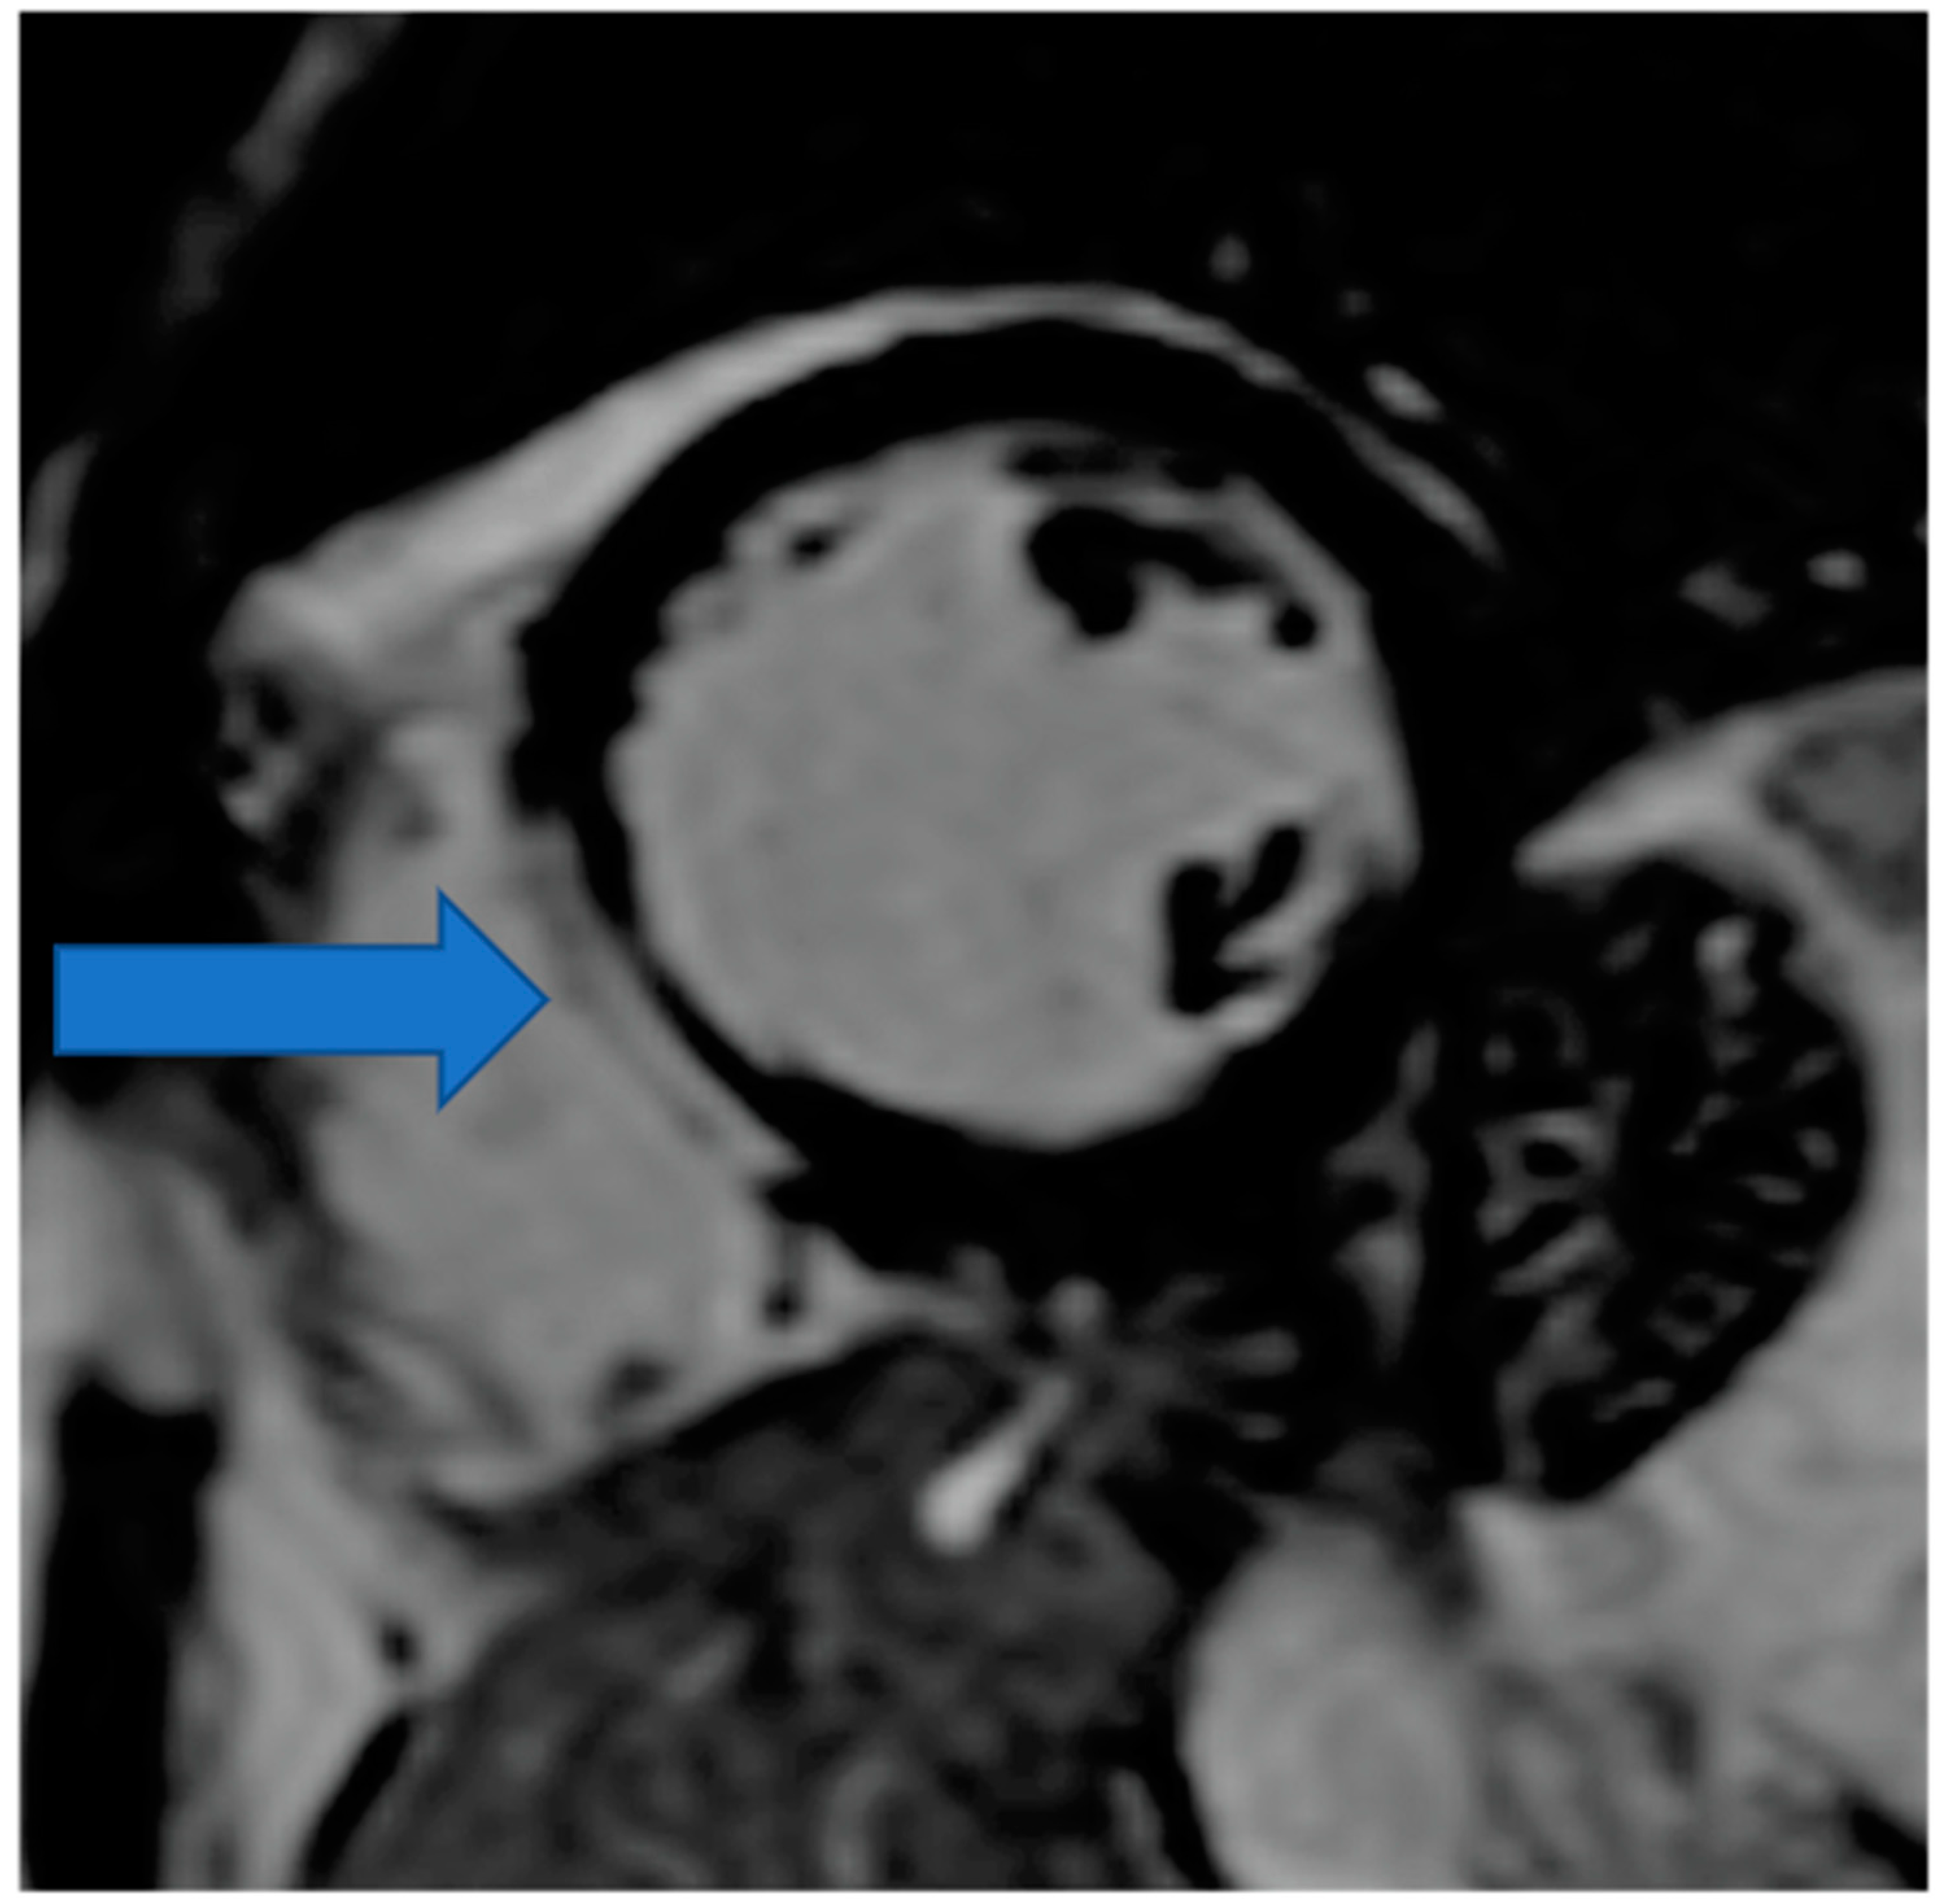

4.4. Non-Invasive Coronary Artery Evaluation

4.5. Myocardial Edema-Fibrosis Assessment